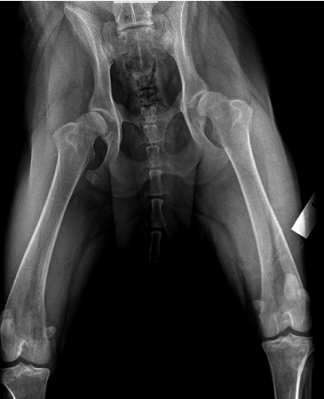

Radiology

East Hilliard Veterinary Services has two state of the art digital imaging systems, one specific for dental imaging and one for full body studies. This radiology equipment allows our veterinarians to detect injury and disease of bone and some soft tissue structures. It is also used to monitor healing or progression of chronic cases. Digital radiology is a fast and reliable diagnostic that we use on a regular basis. Images are stored and can even be sent by telemedicine to radiology specialists for additional consultation.